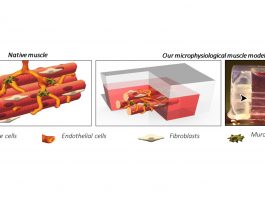

There are a lot of recent developments when it comes to cell therapy. In-between cell and gene therapy is the therapy ‘Gene-modified cell therapy’ (GMCT). GMCT is relevant to any conversation about cell therapy and it’s really one of the most exciting areas of cell therapy right now. At ARM, we track clinical trials with regenerative medicine and one of the things that really jumps out from the latest data is that more than half of the clinical trials in phase one that we are tracking are in GMCT. This is a major development that has happened over the last two years.

In addition to this, another development in cell therapy is CAR T-cell (chimeric antigen receptor T-cell) therapy. Moreover, other adaptive cell therapies are expanding beyond blood disorders to address auto-immune disorders and immune rejection. We’ve seen some exciting advances in allogeneic therapies. There is definitely some interesting clinical developments and encouraging news in allogeneic cell therapies and I think we’ll see some data over the course of 2020 that will also be telling as to the evolution of allogeneic cell therapy.

We are also starting to see some interesting preclinical and clinical activity in allogeneic therapies utilising iPSCs (induced pluripotent stem cells). It is important to note that advances in manufacturing and logistics are easing the administration, delivery and adoption of therapies inside clinical centres. It is an exciting time in cell therapy with the expanding number of clinical trials, different technology approaches, and the integration of gene editing in cell therapy.

Secondly, another challenge facing the sector is manufacturing. The manufacture of these products is very complex compared to traditional pharmaceuticals because they’re so personalised and highly individualised. Therefore, figuring out how to develop a system that allows for efficiencies of scale to be applied to more than one manufacturing processes is a huge challenge for the sector. A lot of time and effort is being focused on this right now and at ARM, we are doing a lot of work in this space. Part of this is to do with the maturation of the field in terms of technological development and implementation, and the development of standards and best practice guidelines.